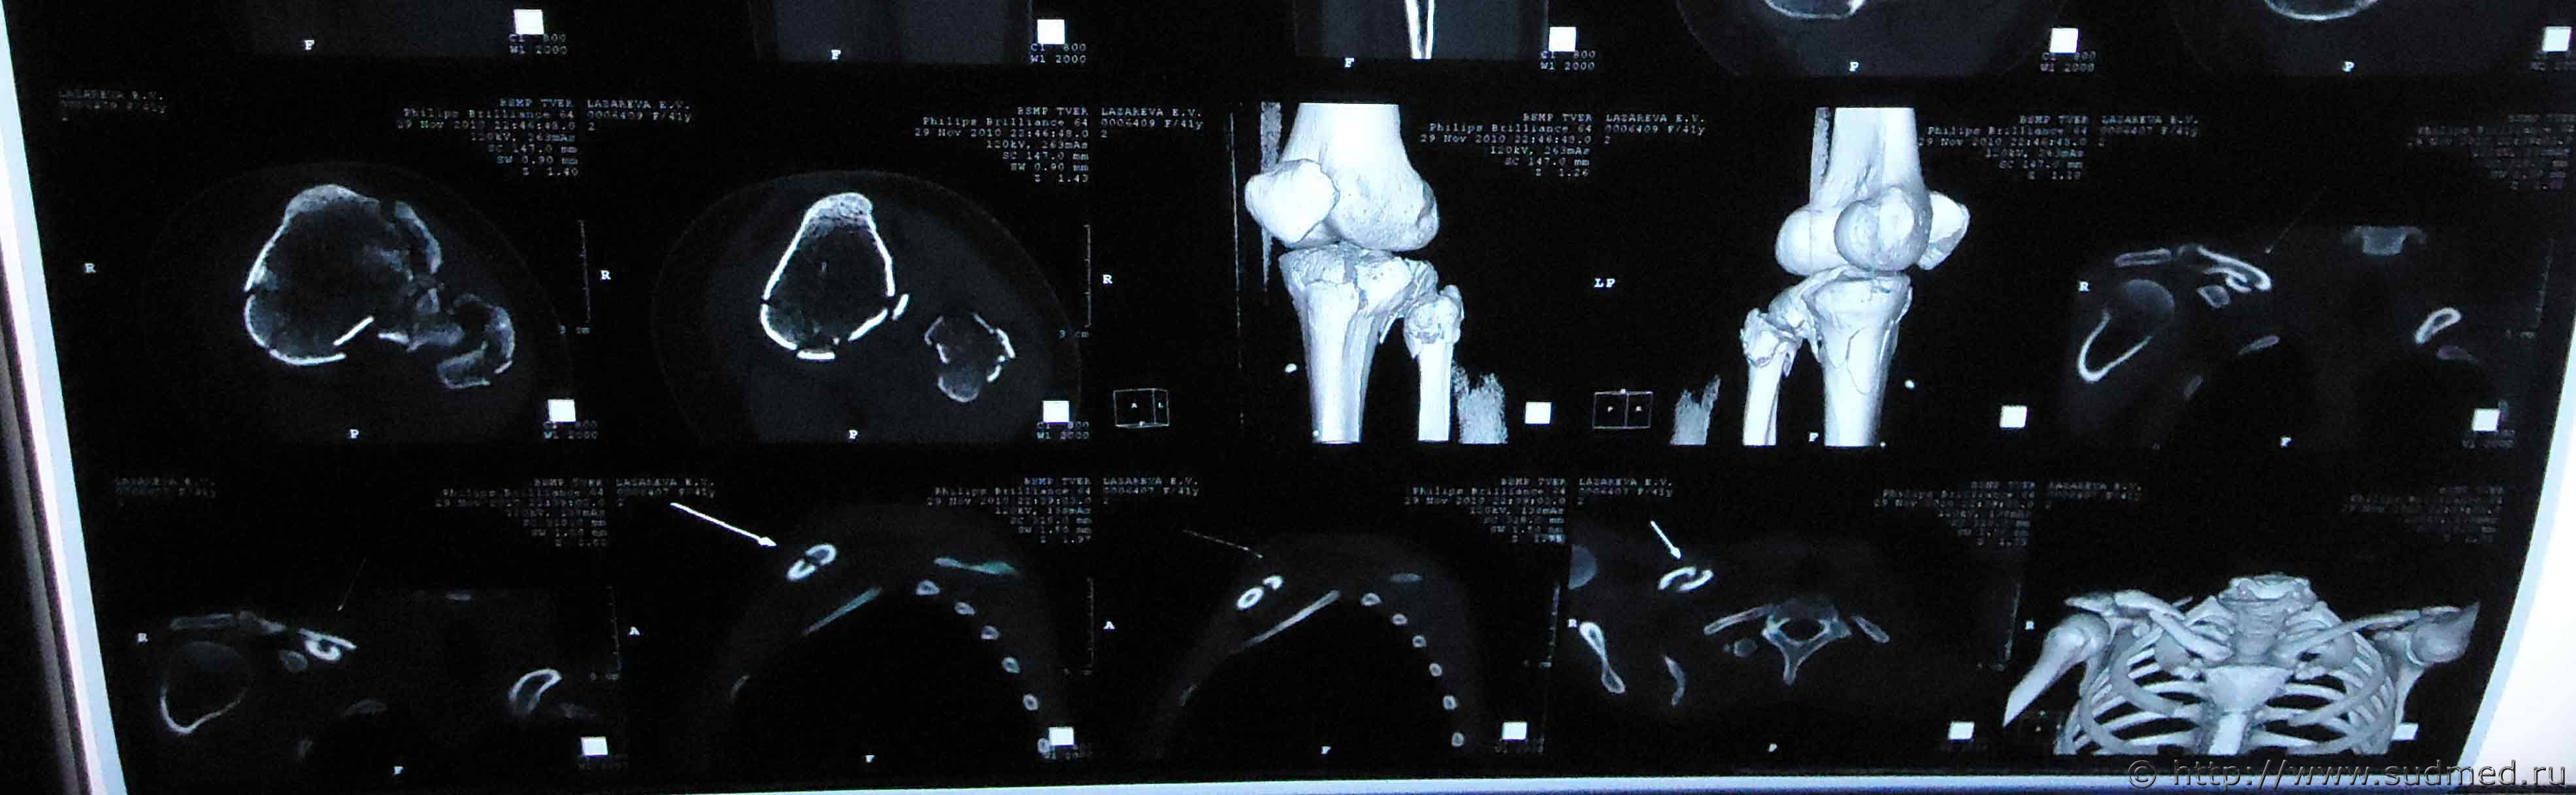

Здравствуйте. На мою жену 2 года назад был совершен наезд, при этом она получила травмы: ЗЧМТ, сотрясение головного мозга, закрытый оскольчатый внутрисуставной перелом проксимального метаэпифиза левой большеберцовой кости со смещением, закрытый оскольчатый перелом проксимального эпифиза левой малоберцовой кости без смещения, закрытый косой перелом правой ключицы средней трети со смещением отломков.

Помогите установить степень тяжести вреда и что делать для обжалования медицинской экспертизы? Снимки прилагаю

Судебная медицина - Прикрепленное изображение Судебная медицина - Прикрепленное изображение Судебная медицина - Прикрепленное изображение Судебная медицина - Прикрепленное изображение Судебная медицина - Прикрепленное изображение